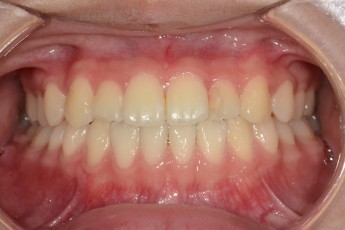

Before

After